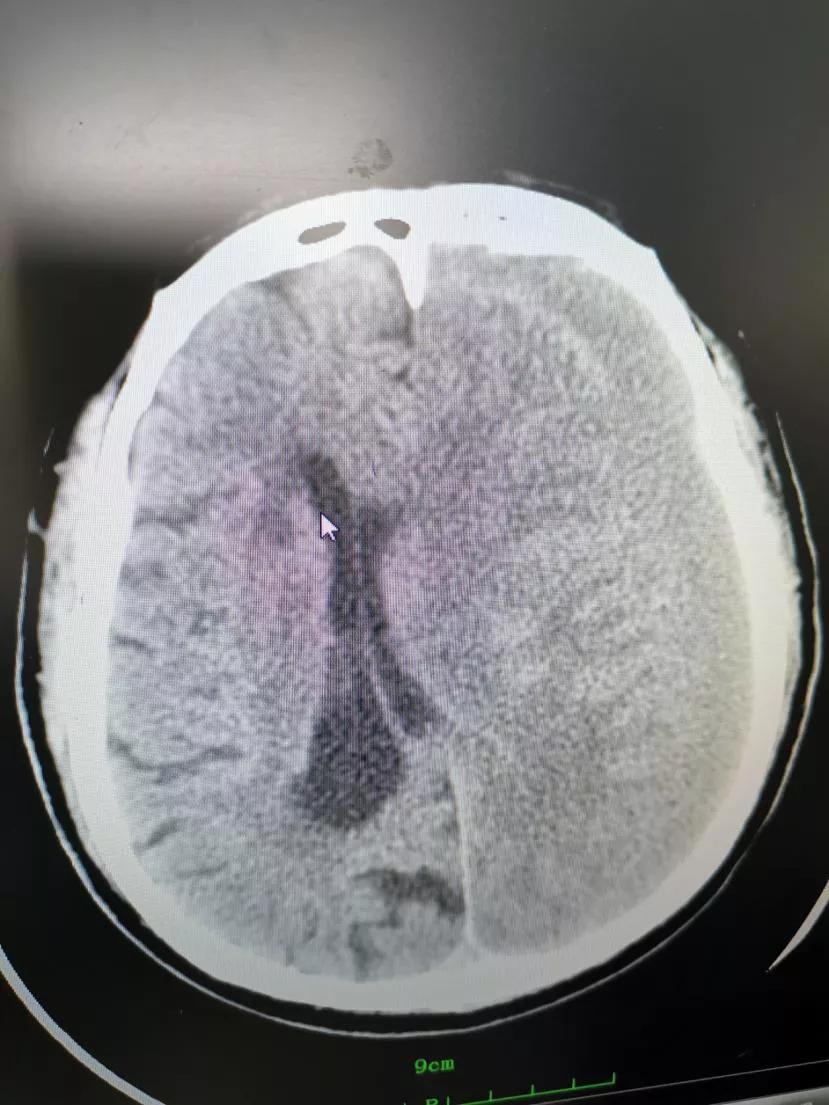

急诊行脑CT提示——

刘老伯左侧额颞顶枕部慢性硬膜下血肿,中线结构明显右移。